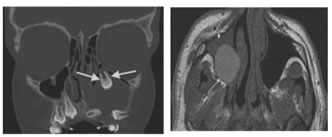

7

Figure7: Odontogenic keratocystic tumor (KCOT) in the maxilla. Axial CT section shows well-defined cyst centred in posterior right maxilla (white arrow heads), with amorphous hyper attenuating central contents (black arrow).